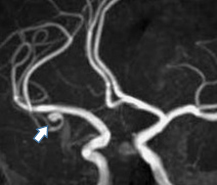

下の画像の患者さんは、突然右手足に力が入らなくなったが少し経って治ったという症状で受診しました。脳内の動脈を描出するMRA検査で左中大脳動脈に狭窄部位(矢印)が見られます。狭くなった動脈の末梢に頭皮の動脈でバイパスを作る手術(浅側頭動脈―中大脳動脈吻合術)を行い、脳梗塞を発症する事なく元気に過ごされています。